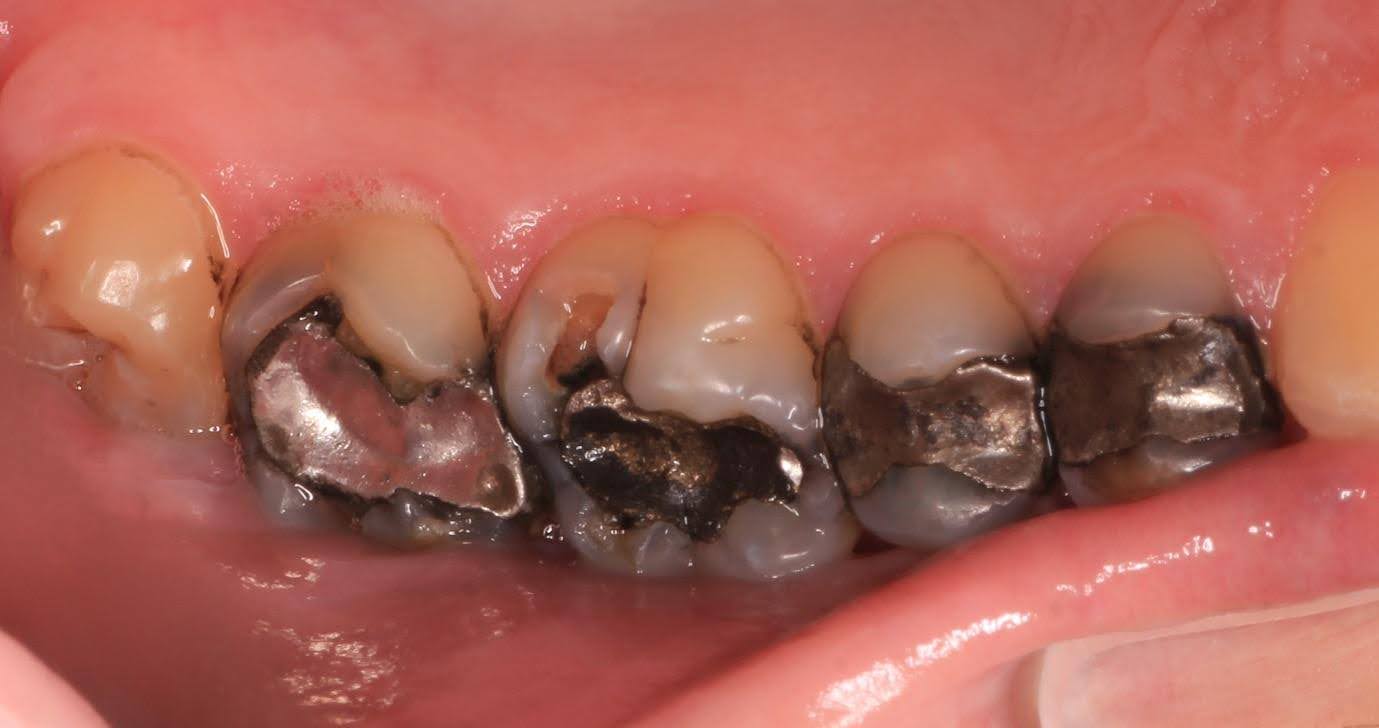

Sequential replacement of failing mercury fillings with porcelain restorations, whilst keeping as much tooth structure intact as possible.